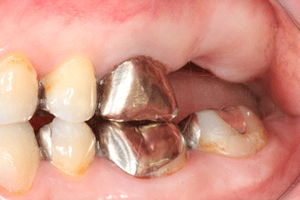

ソケットリフトによる奥歯のインプラント症例

右上に1本のインプラントをした症例です。患者様自身、虫歯で奥歯を失ったため、食生活や、他の歯への負担、歯の移動などを不安なされていたため、インプラントの選択を行なわれました。

術後の写真は、インプラント植立を行なった後6ヶ月後に被せものをはめた状態です。